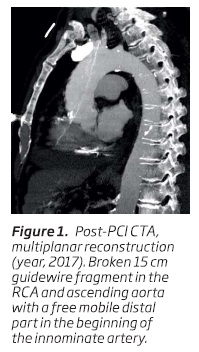

A 65-year-old man underwent PCI due to low threshold angina in 2017, in another Hospital. PCI description highlighted a severe distal right coronary artery (RCA) stenosis. A proximal optimization technique (POT) was performed with a balance middle weight guidewire (BMW, Abbott-Vascular, Santa Clara, CA) placed in the posterior descending artery (PDA). After stenting, the protection PDA guidewire became “jailed” between the deployed stent and the severely calcified vessel wall. After several pullback maneuvers it broke leaving a fragment of approximately 15 cm length in place. Multiple attempts (snare catheter, two-wire rotation technique) went in vain for wire removal. The patient was clinically stable and considering that the risk of further aggressive manipulation could outweigh the benefits it was decided to end the procedure. Post-interventional computed tomography angiography (CTA) revealed the broken guidewire in the RCA and ascending aorta with a free mobile distal part in the beginning of the innominate artery (figure 1).

Although informed about the risks of leaving the wire in place, the patient refused surgical intervention. He underwent a regular follow-up program during which he did not experienced any cardiovascular symptom or shown any deterioration in his left ventricular ejection. Two and a half years later, the patient felt a sudden chest pain and then collapsed. Emergent transthoracic echocardiography revealed the echo-dense wire protruding from the coronary cusp into the ascending aorta and a massive hemopericardium (figure 2).After pericardiocentesis he was transferred to our Institution for emergent cardiac surgery. Intra-operatively, cardiac surgeons found the guidewire fragment perforating the PDA. When pulling the fragment out, it fractured again and only about 8 cm of the distal portion of the wire were recovered. Transesophageal echocardiography no longer demonstrated the wire in the ascending aorta as seen in the beginning of the procedure. After cardiac surgery and hemodynamic stabilization, a CTA was performed revealing a cephalic migration of fragment: now it was entrapped in a tortuous initial portion of the right internal carotid artery and a small pseudoaneurysm was visible at the distal portion of the wire (figure 3.1 and 3.2). CTA axial views suggested that the fragment might be in a subintimal plane (figure 3.3).